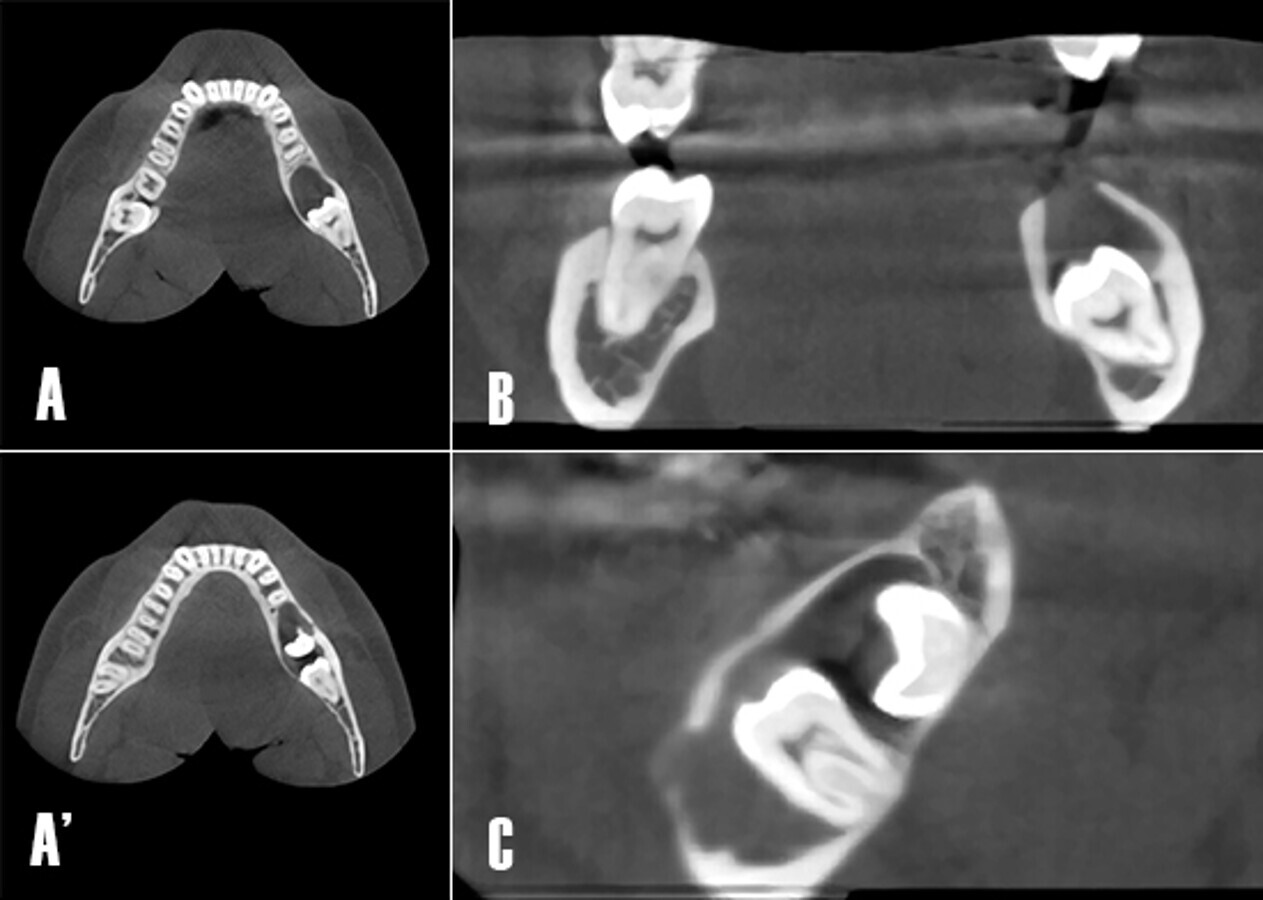

La TCHC (Planmeca ProMax 3D Classic) mostró una extensa imagen osteolítica poco radiodensa en el tercer cuadrante. La lesión era visible en los planos axial, coronal y sagital. Se observó la afectación de la cortical vestibular relacionada a la lesión osteolítica (Fig. 3).

Figura 3. Tomografía computarizada de haz cónico. A) Corte axial. Nótese como la extensión de la lesión osteolítica se extiende en sentido antero posterior afectando la raíz distal de 3.6. A´) Corte axial. En un corte más apical se visualiza la parcialmente la corona de 3.7, y una mayor extensión de la lesión en sentido antero-posterior hasta distal de 3.5. B). Corte coronal. Se observa cómo la lesión osteolítica ha comprometido la integridad de la cortical en sentido craneal. C) Corte axial. La zona poco radiodensa está relacionada a los dientes 3.7 y 3.8 no erupcionados.

En la reconstrucción tridimensional a partir de la TCHC, se pudo observar con mayor claridad la afectación de las corticales vestibular (Fig. 4A) y lingual (Fig. 4B), además se observó la rizólisis de las raíces de los dientes 3.6 y 3.5 (Fig. 4C).